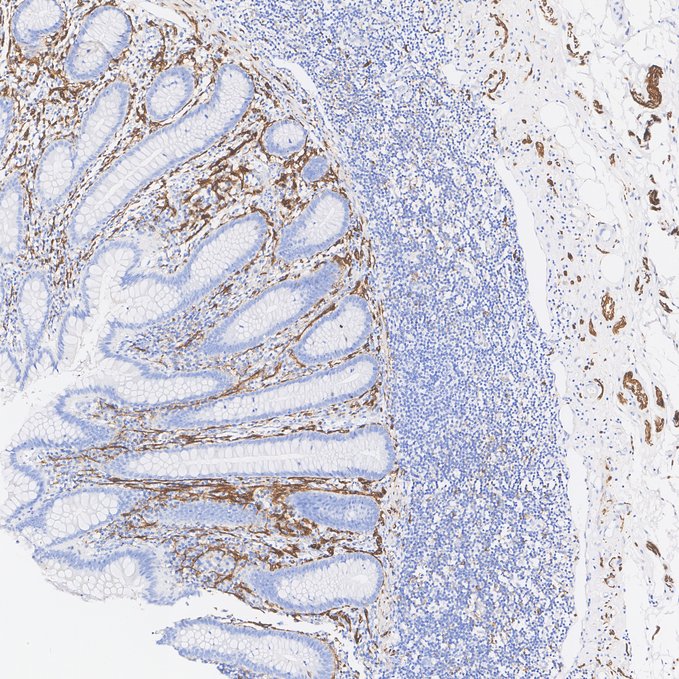

Immunohistochemical analysis of paraffin-embedded human appendix tissue with Rabbit anti-NCAM1 / CD56 antibody (HA723041) at 1/500 dilution.

Heat mediated antigen retrieval with Tris-EDTA buffer (pH 9.0, epitope retrieval solution 2) for 20 mins. The section was incubated with HA723041 for 30 mins at room temperature. The immunostaining was performed on a Leica Biosystems BOND® RX instrument. DAB was used as the chromogen. Tissues were counterstained with hematoxylin and mounted with DPX.

Application: Immunohistochemistry (IHC-P)

Species: Human

Tissue: Appendix

Sample: Paraffin-embedded section

Primary antibody dilution: 1/500

Antigen retrieval: ER2

Platform: Leica Biosystems BOND® RX